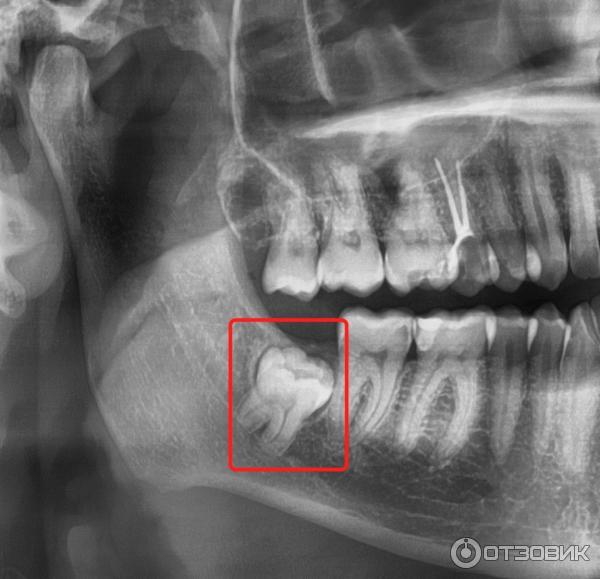

Дентальная галерея: ретинированный зуб клык и его лечение

Раздел: Компас решений